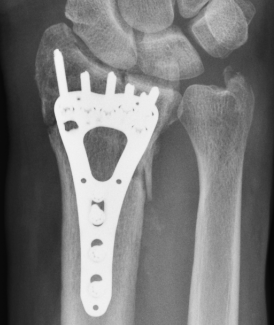

Volar rim fractures

Definition

Very distal fractures

Need distal plates

Low profile plates to protect flexor tendons

Technique

Plate sits distal to watershed line

- variable angle screws

- sit in subchondral bone

- can cause flexor tendon irritation and may need removal

Outcomes

Lari et al Eur J Orthop Surg Traumatol 2023

- systematic review of surgical treatment of volar rim fractures

- 26 studies and 600 patients

- implant removal 22%

- flexor tendon irritation 6%